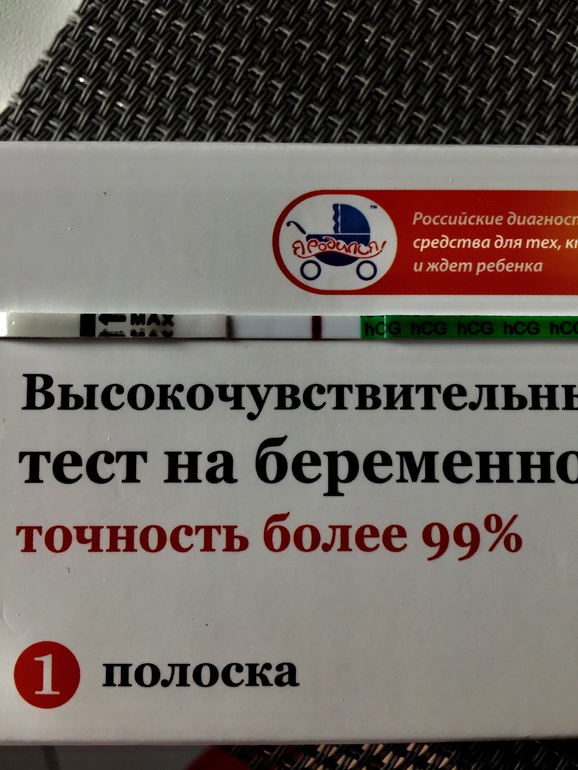

Прошу откликнуться, кто сталкивался. Ночью схватила резкая боль, после ПА. Утром помчала на УЗИ, где ставят диагноз: ЭХО признаки Диффузной формы аденомиоза. Кисты фолликулярной и КЖТ правого яичника. Апоплексии правого яичника.

Через 5ч только приём у Г....